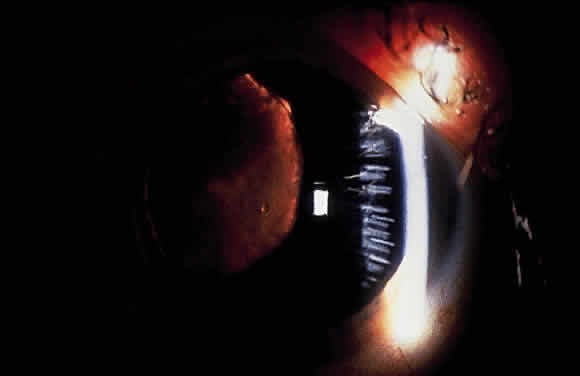

Some patients with XFS exhibit phacodonesis and subluxation of the lens, apparently resulting from degenerative changes in the zonular fibers.45–47 (Fig. 3) Spontaneous dislocation of the lens into the vitreous has been reported.48 In 1970, Bartholomew described 22 spontaneously displaced lenses in 19 patients with the disorder.45 Sixteen of the lenses were subluxated inferiorly. In these eyes, he visualized superior zonular fibers that were coated with exfoliative material and further noted that the zonular breaks generally were present at the ciliary body attachments and not at the lens, leading him to hypothesize that the main degenerative process occurred at the insertion of the zonular fibers to the basement membrane of the ciliary body epithelium. By electron microscopic examination, Schlötzer-Schrehardt and Naumann noted disruption of zonular fiber structure at the ciliary body insertion sites in eyes with XFS but also observed abnormalities at the attachments to the anterior lens capsule.46

Bartholomew also describes phacodonesis in XFS and believes that this represents a probable sign of incipient lens displacement.49 On electron microscopic studies, Futa and Furuyoshi demonstrated marked degenerative changes in the lens zonules of XFS eyes with phacodonesis compared with normal zonular structure in those with no phacodonesis.47 Clinically, iridodonesis in association with phacodonesis may not necessarily be observed because of iris infiltration by exfoliative material or, perhaps, prolonged miotic therapy.